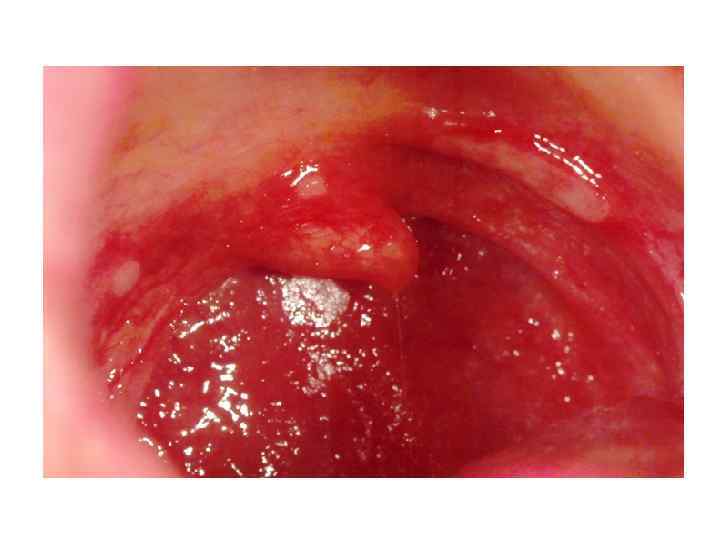

Осмотр собственно полости рта Общий осмотр слизистой оболочки: - цвет; - увлажненность; - наличие участков гиперемии; - наличие отека; - наличие элементов поражения (эрозии, язвы, налет и т. д. ); • - состояние выводных протоков слюнных желез. • • •

Осмотр собственно полости рта Состояние языка: подвижность; состояние сосочков языка; наличие налета; наличие очагов атрофии или гиперплазии сосочков; • наличие отпечатков зубов на боковой поверхности и т. д. • • •

Осмотр собственно полости рта: • • осмотр дна полости рта; осмотр мягкого и твердого неба; осмотр ретромолярных пространств; Осмотр зубных рядов – проводится с помощью стоматологического зеркала и зонда степень подвижности зубов (пинцет); наличие кариозных полостей; цвет (дисколорит) эмали зуба; состояние пломб (сохранность, качество краевого прилегания).